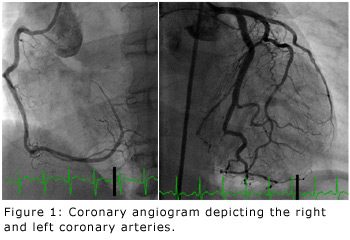

A long, thin, flexible tube, called a catheter, is typically inserted into the leg or arm through a tiny incision (typically less than one-tenth of an inch) at the skin surface. These catheters travel through blood vessels to the heart. Contrast dye is then injected through the catheters and X-rays are taken of the heart. By visualizing the flow of contrast dye within heart arteries and/or heart chambers, detailed information about the heart and its blood supply is obtained (see Figure 1). Due to its minimally invasive approach (very small incision at the skin surface), a cardiac catheterization is usually very well-tolerated without significant discomfort to the patient. The patient is required to lay flat on his/her back for the duration of the procedure. Routinely, lidocaine is injected at the skin surface to numb the skin and tiny catheters are then inserted. Since there are no nerves inside the blood vessels, the patient does not feel the catheters inside the body once they have been inserted. Sedation medications typically are provided to the patient before and during the procedure, however, it is much safer for the patient to have this procedure performed while awake with minimal sedation as opposed to under general anesthesia with use of a breathing tube.